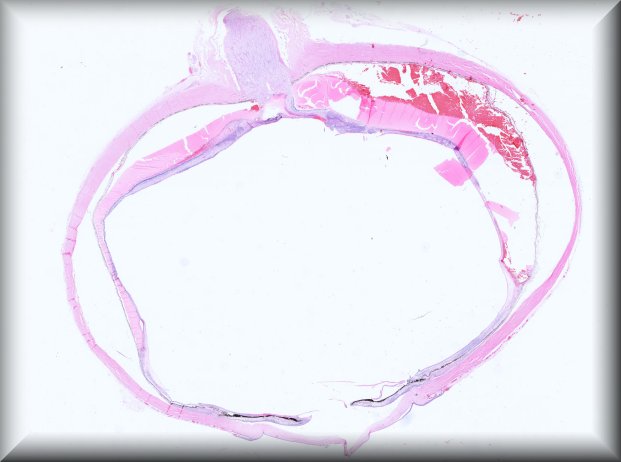

Martina Herwig-Carl (Bonn): 57 year old woman with a blind painful eye and history of intrvitreal bevacizumab injections, tumour biopsy and brachytherapy for uveeal melanoma followed by several proceedures for high intraocular pressure resulting finally in enucleation. |

![]() |